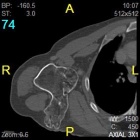

68 yo male with complaints of right shoulder pain with repetitive activities and modified with rest. History of multiple orthopaedic surgeries in the past. He denies history of trauma or constitutional symptoms.

PE: Elderly male in good overall health. Short stature. Palpable mass in posterior right shoulder. Nontender w/o edema or overlying skin changes. Limited ROM in all dimensions. NVI w/o LAN.